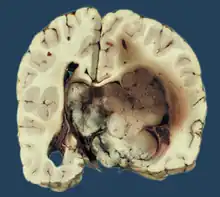

Choroid plexus tumors are divided into three categories by the World Health Organization (2016):[9] papillomas (grade I), atypical tumors (grade II), and carcinomas (grade III). Less than two mitotic figures per 10 high power fields are present in CPPs, two to five are present in atypical ones, and more than five are present in carcinomas. The tumors are visible as pink, soft, spherical lumps with erratic projections and considerable vascularity.

Plexuspapillom Detail

Plexuspapillom Overview